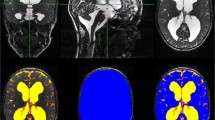

In childhood hydrocephalus, both the amount of cerebrospinal fluid and the brain volume are relevant for the prognosis of the development and for therapy monitoring. Since classical planar measurements of ventricular size are subject to strong limitations, imprecise and neglect brain volume, 3D volumetry is most desirable. We used and evaluated the robust segmentation algorithms of the freely available FSL-toolbox in paediatric hydrocephalus patients before and after specific therapy.

Retrospectively 76 pre- and postoperative high-resolution T2-weighted MRI sequences (true FISP, 1 mm isovoxel) were analyzed in 38 patients with paediatric hydrocephalus (mean 4.4 ± 5.1 years) who underwent surgical treatment (ventriculo-peritoneal (VP) shunt n = 22, endoscopic third ventriculostomy (ETV) n = 16). After preprocessing, the 3D-datasets were skull stripped to estimate the inner skull surface. Following, a 2 class segmentation into different tissue types (brain matter and CSF) was performed. The volumes of CSF and brain were calculated.

The method could be implemented in an automated fashion in all 76 MRIs. In the VP shunt cohort, the amount of CSF (p < 0.001) decreased. Consecutively brain volume increased significantly (p < 0.001). Following ETV, CSF volume (p = 0.019) decreased significantly (p = 0.012) although the reduction was less pronounced than after shunt implantation. Brain volume expanded (p = 0.02).

A reliable automated segmentation of CSF and brain could be performed with the implemented algorithm. The method was able to track changes after therapy and detected significant differences in CSF and brain volumes after shunting and after ETV.